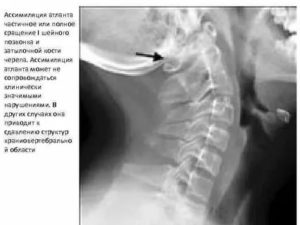

Клинический интерес представляет также такая патология краниовертебрального перехода, как ассимиляция атланта, т.е. частичное или полное сращение его с затылочной костью. Это приводит к ограничению движений в верхнем шейном и нестабильности в нижнем шейном отделах позвоночника. Кроме того возможна компрессия мозговых структур данной области с соответствующей клинической картиной.

Аномалия кранио-вертебрального перехода: ассимиляция С1, затылочной кости, зубовидного отростка С2 позвонка; базиллярная импрессия. Ротационное смещение С1 позвонка, гипертрофия боковых масс тела С1 позвонка. Стеноз большого затылочного отверстия. Очаговая миелопатия на уровне С2 позвонка.

Сращение правых отделов боковых масс атланта и основания затылочной кости (синостоз правого атланто-окципитального сочленения).